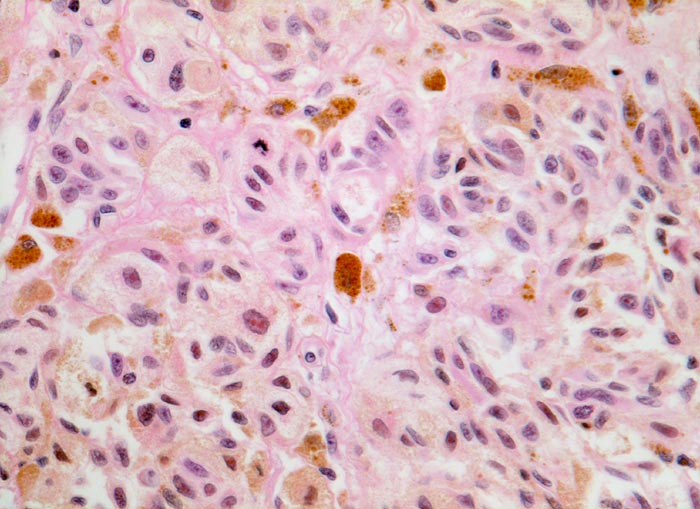

Atypische pigmentierte Zellen mit reichlich Zytoplasma und vergrösserten atypischen Kernen mit prominenten eosinophilen Nukleolen. Mitose. Zwischen den Tumorzellen Melanophagen mit grobgranulärem intrazytoplasmatischem Pigment.

Stellenweise erhabene, unregelmässig begrenzte und inhomogen gefärbte braun-schwarze Hautläsion.

Der Nachweis von Mitosen in intradermal gelegenen Melanozyten spricht für das Vorliegen eines malignen Melanoms.